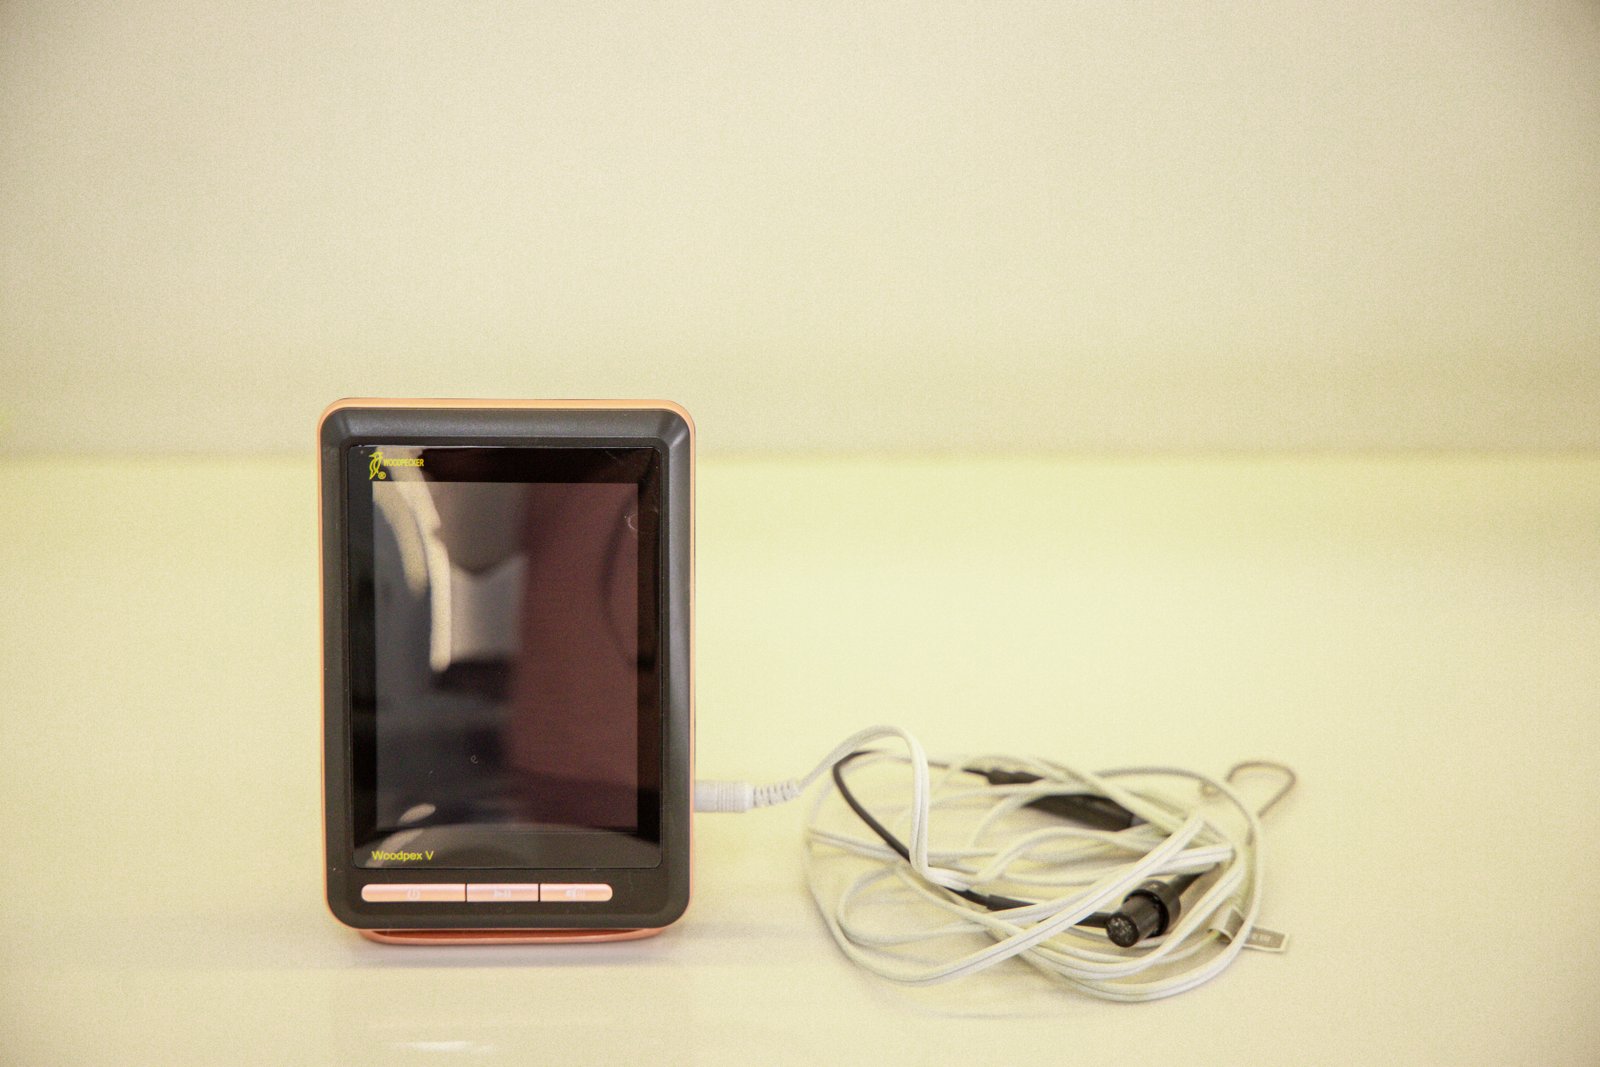

Specialized endodontic care to save infected teeth and relieve pain.

See every stage of our treatments with clear, step-by-step visuals that reflect our precision and care.